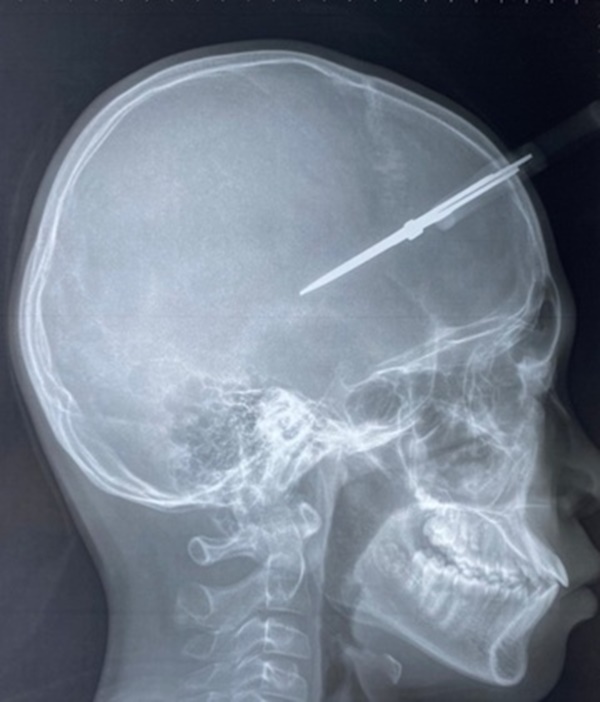

Theo thông tin khai thác, tai nạn xảy ra trong ngày đi học cuối cùng trước kỳ nghỉ Tết, khi bé H. chơi đùa với bạn cùng lớp. Thời điểm nhập viện, bé tỉnh táo, chiếc kéo vẫn cắm chặt vào đầu ở vùng thái dương phải. Phim chụp cho thấy cây kéo đã xuyên qua xương sọ, vào trong hộp sọ của bệnh nhi.

Cây kéo xuyên qua xương sọ của bệnh nhi. Ảnh: BVCC.

Ở tình huống này, vị trí của cây kéo nằm ở vùng thái dương, nơi có động mạch màng não giữa đi qua, rất có thể gây đứt động mạch, máu tụ ngoài màng cứng.